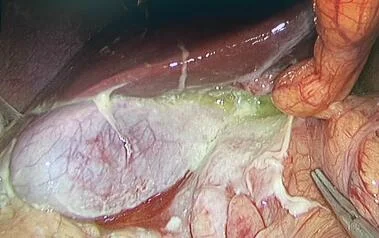

- Phẫu thuật nội soi bóc u nang buồng trứng, bóc u xơ tử cung, cắt tử cung qua nội soi, phẫu thuật tạo hình buồng tử cung (Strasman)